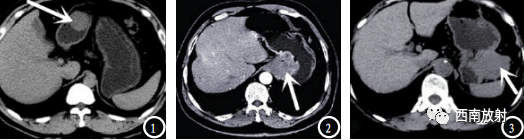

▲病例:胃肠道不同部位的间质瘤形态表现。([2]廖 月.胃肠道间质瘤患者 超声和MSCT征象特 点分析[J].中国CT和MRI杂志.2019.17(1):101-103.)

▲小肠间质瘤,肿块巨大,超过10cm,实质内见多发钙化灶;

▲小肠间质瘤,肿块巨大,超过10cm,实质内见多发钙化灶;动脉期肿块不均匀强化,见斑片状坏死区及环状或花边状改变[4]。

▲小肠间质瘤,肿块巨大,超过10cm,实质内见多发钙化灶;动脉期肿块不均匀强化,见斑片状坏死区及环状或花边状改变。静脉期强化更加明显。